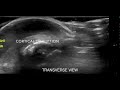

RSV Bronchiolitis Subpleural Consolidation on Mindray TE-X linear array transducer lung preset

6 m.o. Boy RR 40s, subcostal retractions with head bobbing, RSV pcr positive. Lung US using Mindray TE-X linear array transducer detects subpleural consolidation.

Images captured with Mindray TE-X, linear array transducer on lung preset.